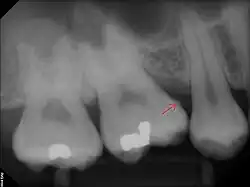

The following minerals are detectable in calculus by X-ray diffraction:

Subgingival calculus forms below the gumline and is typically darkened in color by the presence of black-pigmented bacteria,[18] whose cells are coated in a layer of iron obtained from heme during gingival bleeding.[19] The reason fossilized bacteria are initially attracted to one part of the subgingival tooth surface over another is not fully understood. However, once the first layer is attached, more calculus components are naturally attracted to the same places due to electrical charge. This is because the calcium phosphate salts contained in them exist as electrically unstable ions (unlike calcium phosphate, the primary component of teeth). The fossilized bacteria pile up rather haphazardly, while free-floating ionic components (calcium phosphate salts) fill in the gaps.[15]